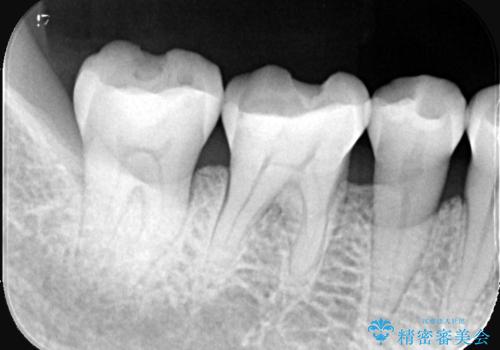

- 主訴:プラスチックの劣化が気になる。

咬合面にCR(コンポジットレジン)修復が広範囲にされており、劣化のしにくさや審美性からセラミックインレーでのやり替えとなりました。

今回残存歯質量から破折のリスクを説明し、クラウンでのやり替えも提案しましたが歯質切削量が多くなることから一度インレーで様子を見ることとなりました。